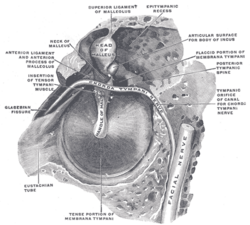

| The right eardrum with the hammer and the chorda tympani, viewed from within, from behind, and from above (malleus visible at center) | ||

Parts of the Malleus

The malleus has several important parts:

- Head: This is the largest, rounded part at the top. It connects to the incus.

- Neck: A narrower section that connects the head to the handle.

- Handle (or Manubrium): This long, thin part attaches to the eardrum.

- Processes: These are small bumps that stick out from the bone. They help it connect to other parts of the ear.

The malleus is positioned so its head is at the top and its handle points downwards towards the eardrum.